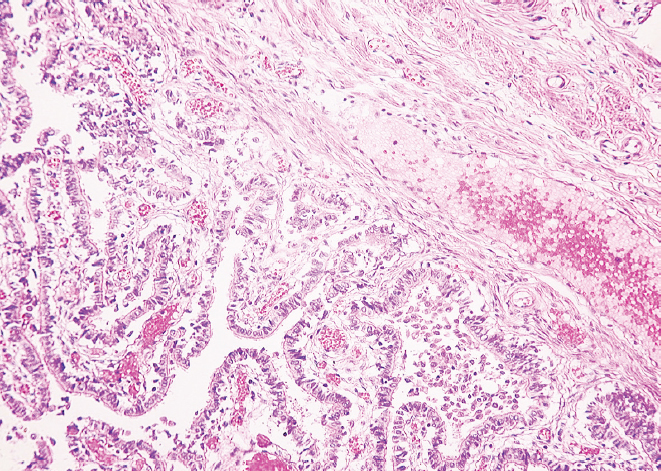

Результаты. Установлено уменьшение показателей наружного диаметра перешейка и воронки обеих маточных труб женщин от молодого возраста к старческому (p < 0,01). В старческом возрасте определено преобладание параметров наружного диаметра перешейка и воронки правой маточной трубы в сравнении с показателями левой маточной трубы (p < 0,01), наряду с этим в молодом возрасте выявлена лишь тенденция к превалированию значений диаметра перешейка и воронки правой маточной трубы (p > 0,05). Гистологическое исследование показало наличие утолщенных складок слизистой оболочки и уплощенного эпителия в исследуемых областях у женщин старческого возраста, истончение слоев мышечной оболочки и разрастание соединительной ткани в сравнении с образцами, взятыми для исследования у женщин молодого возраста.

Заключение. Морфологическая перестройка перешейка и воронки маточных труб от молодого к старческому возрасту заключается в утолщении складок слизистой оболочки, уплощении эпителия, разрастании соединительной ткани в стенке и уменьшении их наружного диаметра с преобладанием параметров в правой маточной трубе.